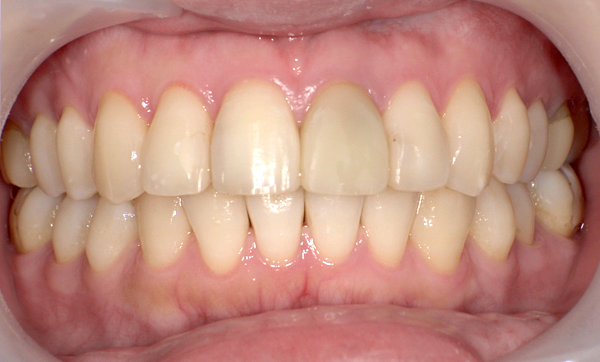

症例:上下顎の部分矯正

症例_007 「出っ歯」症例

治療期間:9ヶ月金額:54万円+税60代女性出っ歯捻転歯

| Before | After |

|---|---|

症例_006 「出っ歯」症例

治療期間:1年2ヶ月金額:54万円+税40代女性出っ歯捻転歯